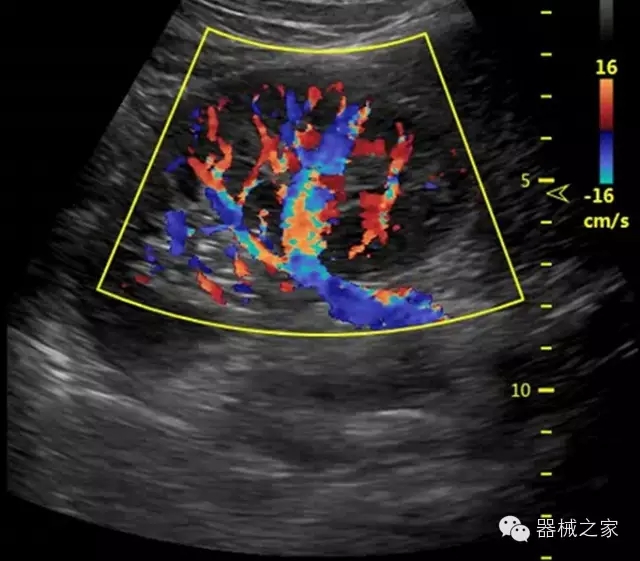

臨床圖片賞析

·亞陣元技術(shù):獨(dú)有的亞陣元技術(shù),對獨(dú)立晶片做二次切割,減少旁瓣偽像,增加臨床診斷的準(zhǔn)確性;

·μ-Scan微米成像技術(shù):開立獨(dú)有的μ-Scan技術(shù),還原出真實細(xì)膩、層次對比優(yōu)異的二維圖像;

·智能微血流成像技術(shù):智能微血流捕捉技術(shù)可以提取出隱藏在背景噪聲中的弱血流信號,大大提高低速血流的敏感性;